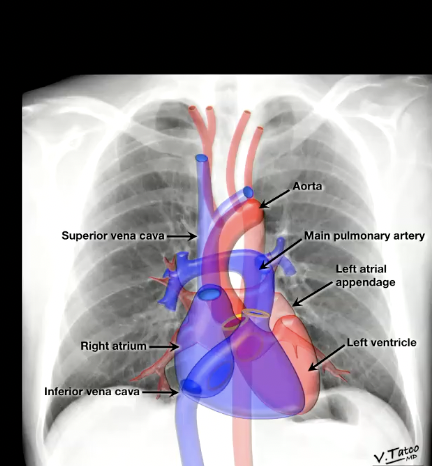

What is the systemic approach to identify and evaluate key structures in a chest radiograph?

identify all of these

Identify Lungs, heart (if you can the different parts too), aorta, and mediastinum on chest XRay

image